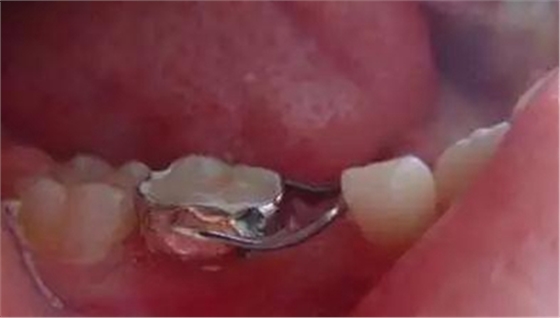

③帶環(huán)絲圈式間隙保持器。

磨牙齲壞,引起牙冠近遠(yuǎn)中徑縮??;另殘根及早失牙等可造成鄰牙移動(dòng);乳磨牙的牙髓、牙周組織感染,引起牙根吸收障礙,不能正常脫落。皆會(huì)造成恒牙替換位置不足,導(dǎo)致恒牙錯(cuò)位、異位或萌出障礙[1]。我們?cè)谂R床工作中制作絲圈式間隙保持器解決此問題,從而保持了牙弓的長度和寬度,使繼承恒牙在合適位置正常萌出,取得了較好的臨床效果 。

制作:在基牙上做帶環(huán)或全冠,再在其上焊接絲圈,絲圈的頰舌徑比后繼恒牙的頰舌徑稍寬。絲圈與牙尖接觸位置要在其遠(yuǎn)中最突點(diǎn)或稍下方。與第一恒磨牙接觸點(diǎn)應(yīng)在近中外形高點(diǎn)。